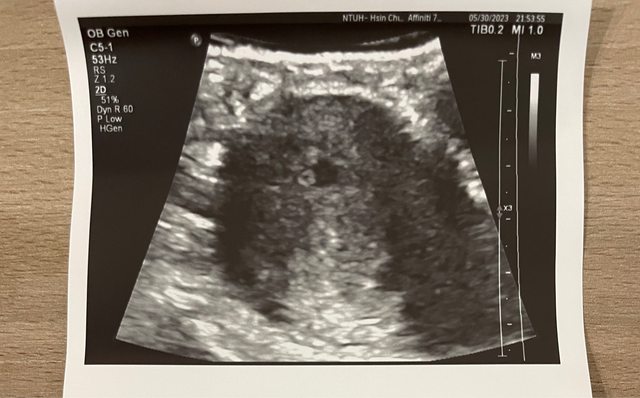

大家好,我今年31歲,跟先生結婚半年多,四月開始積極懷孕,試一個月就懷孕,抱著感 恩的心情迎接這個孩子,原本以為這樣的幸運可以好好陪伴到孩子出生。 目前懷孕按經期週數是7w6D 最後一次經期是4/13,週期算規律28-32天,因為積極準備懷孕所以有驗排卵試紙,排卵 高峰是4/28-29,較app預估晚2-3天。 5/12-5/14 連續驗孕,用不同牌子、形式的驗孕盤/筆,都淺淺兩條才敢確定懷孕 5/22 第一次就診,照腹部超音波確定子宮內懷孕,胚囊大小0.5cm(5w4d)並告知醫師有 微微咖啡色分泌物,量不多,開優潔通口服,一天四次,共一週份,但預約下次回診時間 是兩週後。 因為查了許多早期出血資訊,又擔心只有一週用藥,怕不能撐到兩週後回診,所以隔兩天 (5/25)就去了公司附近的婦產科看診詢問,醫師照腹超找不到,改陰超看,說我的胚囊 按週數來看偏小,只有0.56,可能需要校正一週,但還是先觀察出血狀況,並以原醫院醫 師開藥為主,他額外沒開藥,並且告知下週胚囊應該長到一公分為佳。 這位醫師表達的方式讓我有點擔心,所以又掛了住家附近的婦產科(以生殖醫學為專長) 隔兩天去看診。 而微微的咖啡色分泌物狀況,自5/21-5/26即停止,看起來就只是排出一些分泌物的樣子 ,沒有血塊、沒有鮮紅、沒有其他異常。 5/27 到生殖為主的婦產科看診,醫師說大小確實偏小(0.75cm),以滿六週週數應該每 天大0.1cm,並且預估七週必須出現心跳,但是內診檢查沒有血塊、裡面很乾淨,醫師推估 咖啡色分泌物只是過去未排乾淨的東西而已,開了一週優潔通讓我用塞劑方式使用。 其實到5/27看診完,我反而比較放心,因為知道胚囊一直有在成長,也許是晚一點排卵、 晚一點受精,所以發展的慢一些,也爬文版上有許多到八週、十週才出現胎心的狀況,被 增強了信心,我相信我的孩子只是走得慢一點,但不代表他沒有在長大。 5/30 為了預防萬一,回原醫院看診,並告知咖啡色分泌物已經不見,但醫師說可以持續 使用當作「施肥」給營養。這天照腹超1.16cm醫師說正常,並與5/27相比也有趕上一天0. 1cm的進度,詢問醫師有沒有卵黃囊,也找到了,很飽滿、很圓,心情因而非常放鬆快樂 。見圖。 https://i.imgur.com/jiNwWJv.jpg